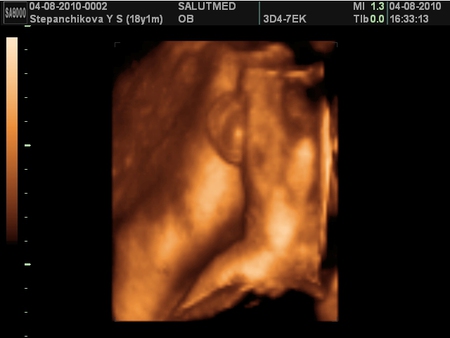

Ходили на 3D УЗИ) в восторге) узи по идеи последнее) дальше только личная встреча с малышом)) Вот подробный отчет:

ну вот и фотки малыша для полного заключения)